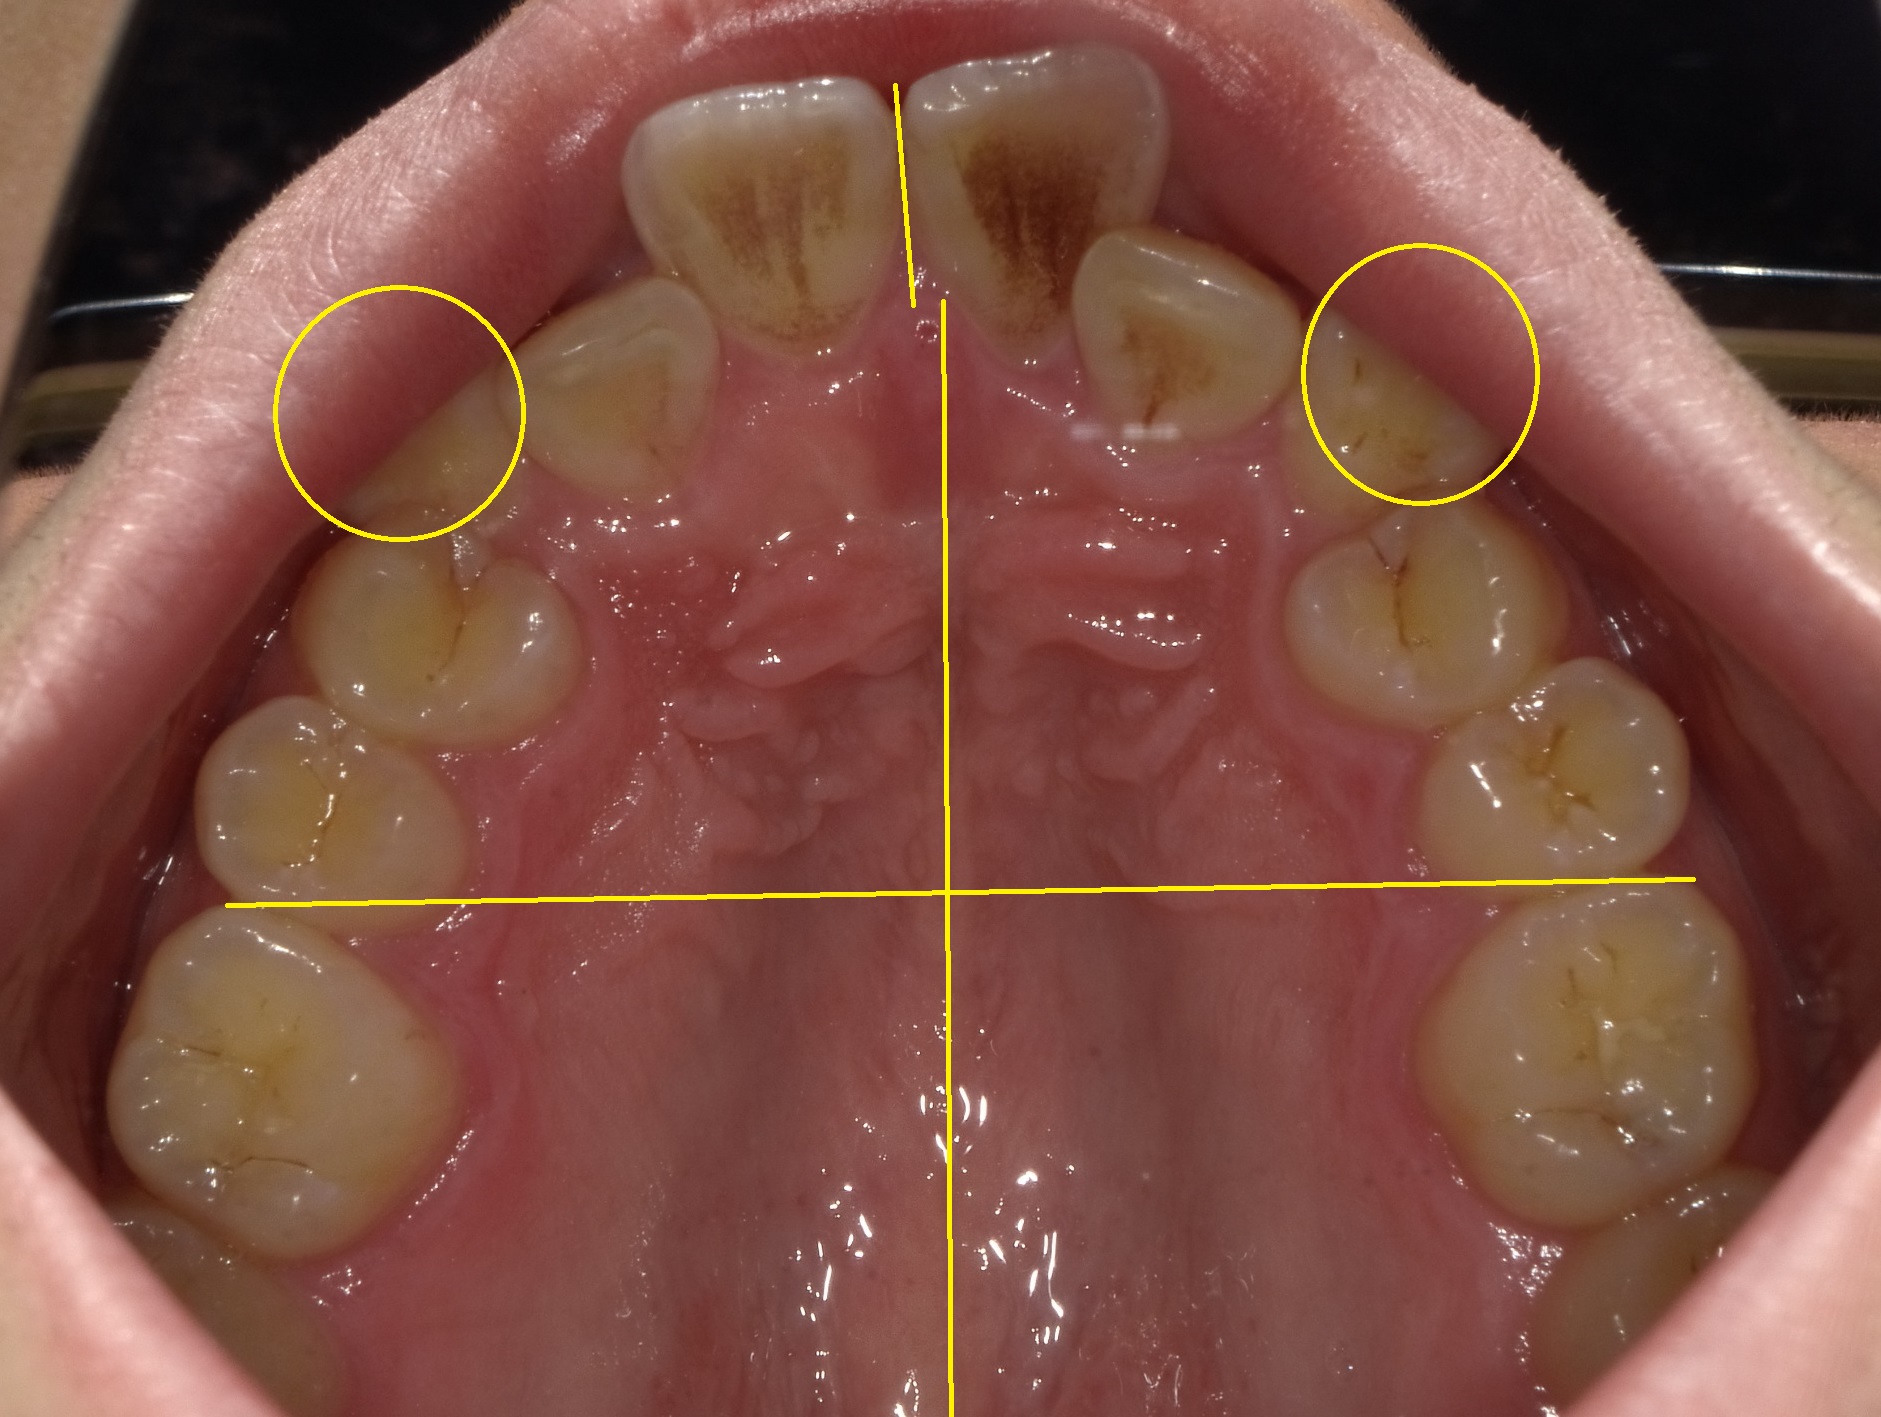

上の歯並びです。

下から見ると大きくズレてはいないように見えますが、顎の正中線や隠れた八重歯(口が小さく唇に隠れている)を表記すると

顎の正中線(真ん中の線)から見ると、上の前歯が右側(画像では左)にヨレテいるのが分かります。

また、左右の犬歯も大きく歯の列からはみ出しています。